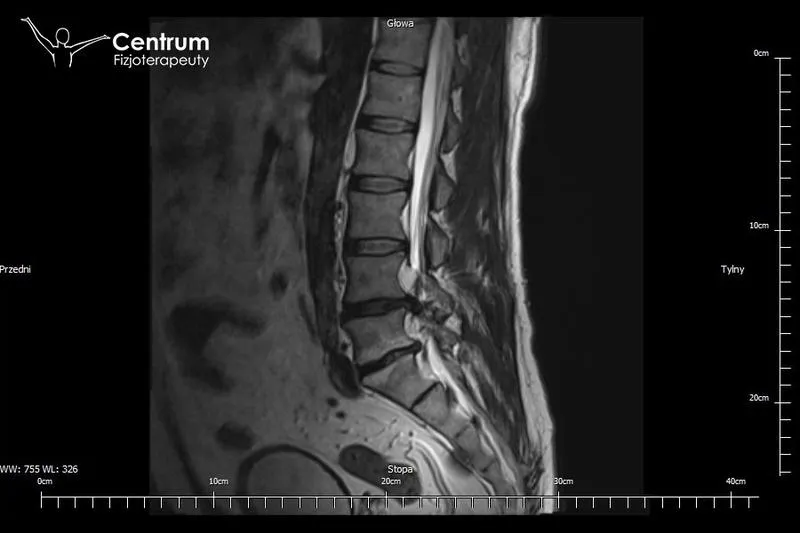

Operacja przepukliny kręgosłupa wywołuje dreszcze nawet u największych twardzieli. Wiele osób kojarzy ten zabieg z igłami, skalpelami oraz szpitalnym klimatem, a pomimo to sporo ludzi wciąż ma wątpliwości co do jego konieczności. Przepuklina kręgosłupa oznacza przesunięcie jądra miażdżystego przez uszkodzony pierścień włóknisty i bez wątpienia jest poważnym problemem. Objawy bywają na tyle dotkliwe, że obejmują nie tylko umiarkowany ból, lecz także promieniowanie, drętwienie oraz inne nieprzyjemne dolegliwości. Jak więc ocenić, czy operacja to jedyna droga do zdrowia?